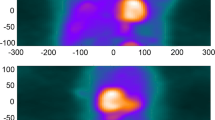

The 600 images were shown as pairs (NMC and DDMC) to two observers (IA, MM) in the format of short, horizontal and vertical long axis slices obtained from Cedars Sinai QPET (Cedars Sinai, Los Angeles, CA, United States). All images were blinded, to the extent that the observers did not know which image was NMC and which was DDMC, and randomized. The two observers were asked to define a Visual Difference Score (VDS) of 0, 1 or 2, which represented the following: 0: no difference perceivable between the images; 1: a subtle difference perceivable between the images and 2: a clear difference between the images. Areas that the observers were asked to take note of were homogeneity and intensity of uptake in the myocardium, separation between the myocardium and surrounding extra-cardiac activity and clarity of the ventricular cavity. Figure 1 gives examples of image pairs rated a VDS of 1 and 2. Following assessment by the two observers, any differences in VDS classification across image pairs were discussed jointly and a consensus score was assigned to produce a single table of values.

Demonstration of characteristics that were used to attribute the corresponding visual difference scores (VDS) for non-motion-corrected (NMC) compared with the motion-corrected images (DDMC). Image pair (A) shows subtle improvement to the separation of the inferior wall from extra-cardiac activity; image pair (B) shows subtle improvement to the inferior wall intensity; image pairs (C) and (D) show clear improvement to the overall definition and intensity of the myocardium, while image pair (D) also shows clear improvement of the separation of the inferior wall from extra-cardiac activity